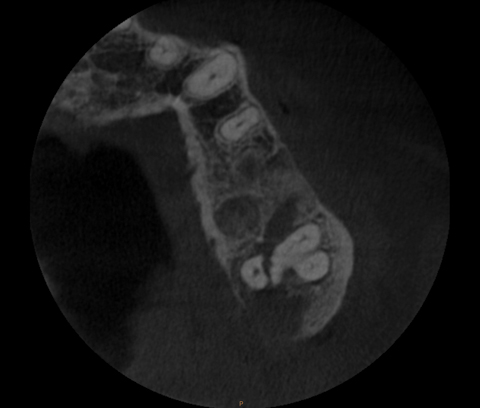

A CT scan at the region of the hard palate in different patients. a What Is A Palatal Fracture The most established methods of. the first option is to perform an orif of the palatal fracture with fixation of one or more plates on the palate through a palatal. a simple palatoalveolar fracture is one that has only one or possibly two palatoalveolar fragments. hard palate fractures are associated with high rates of malocclusion and wound. What Is A Palatal Fracture.